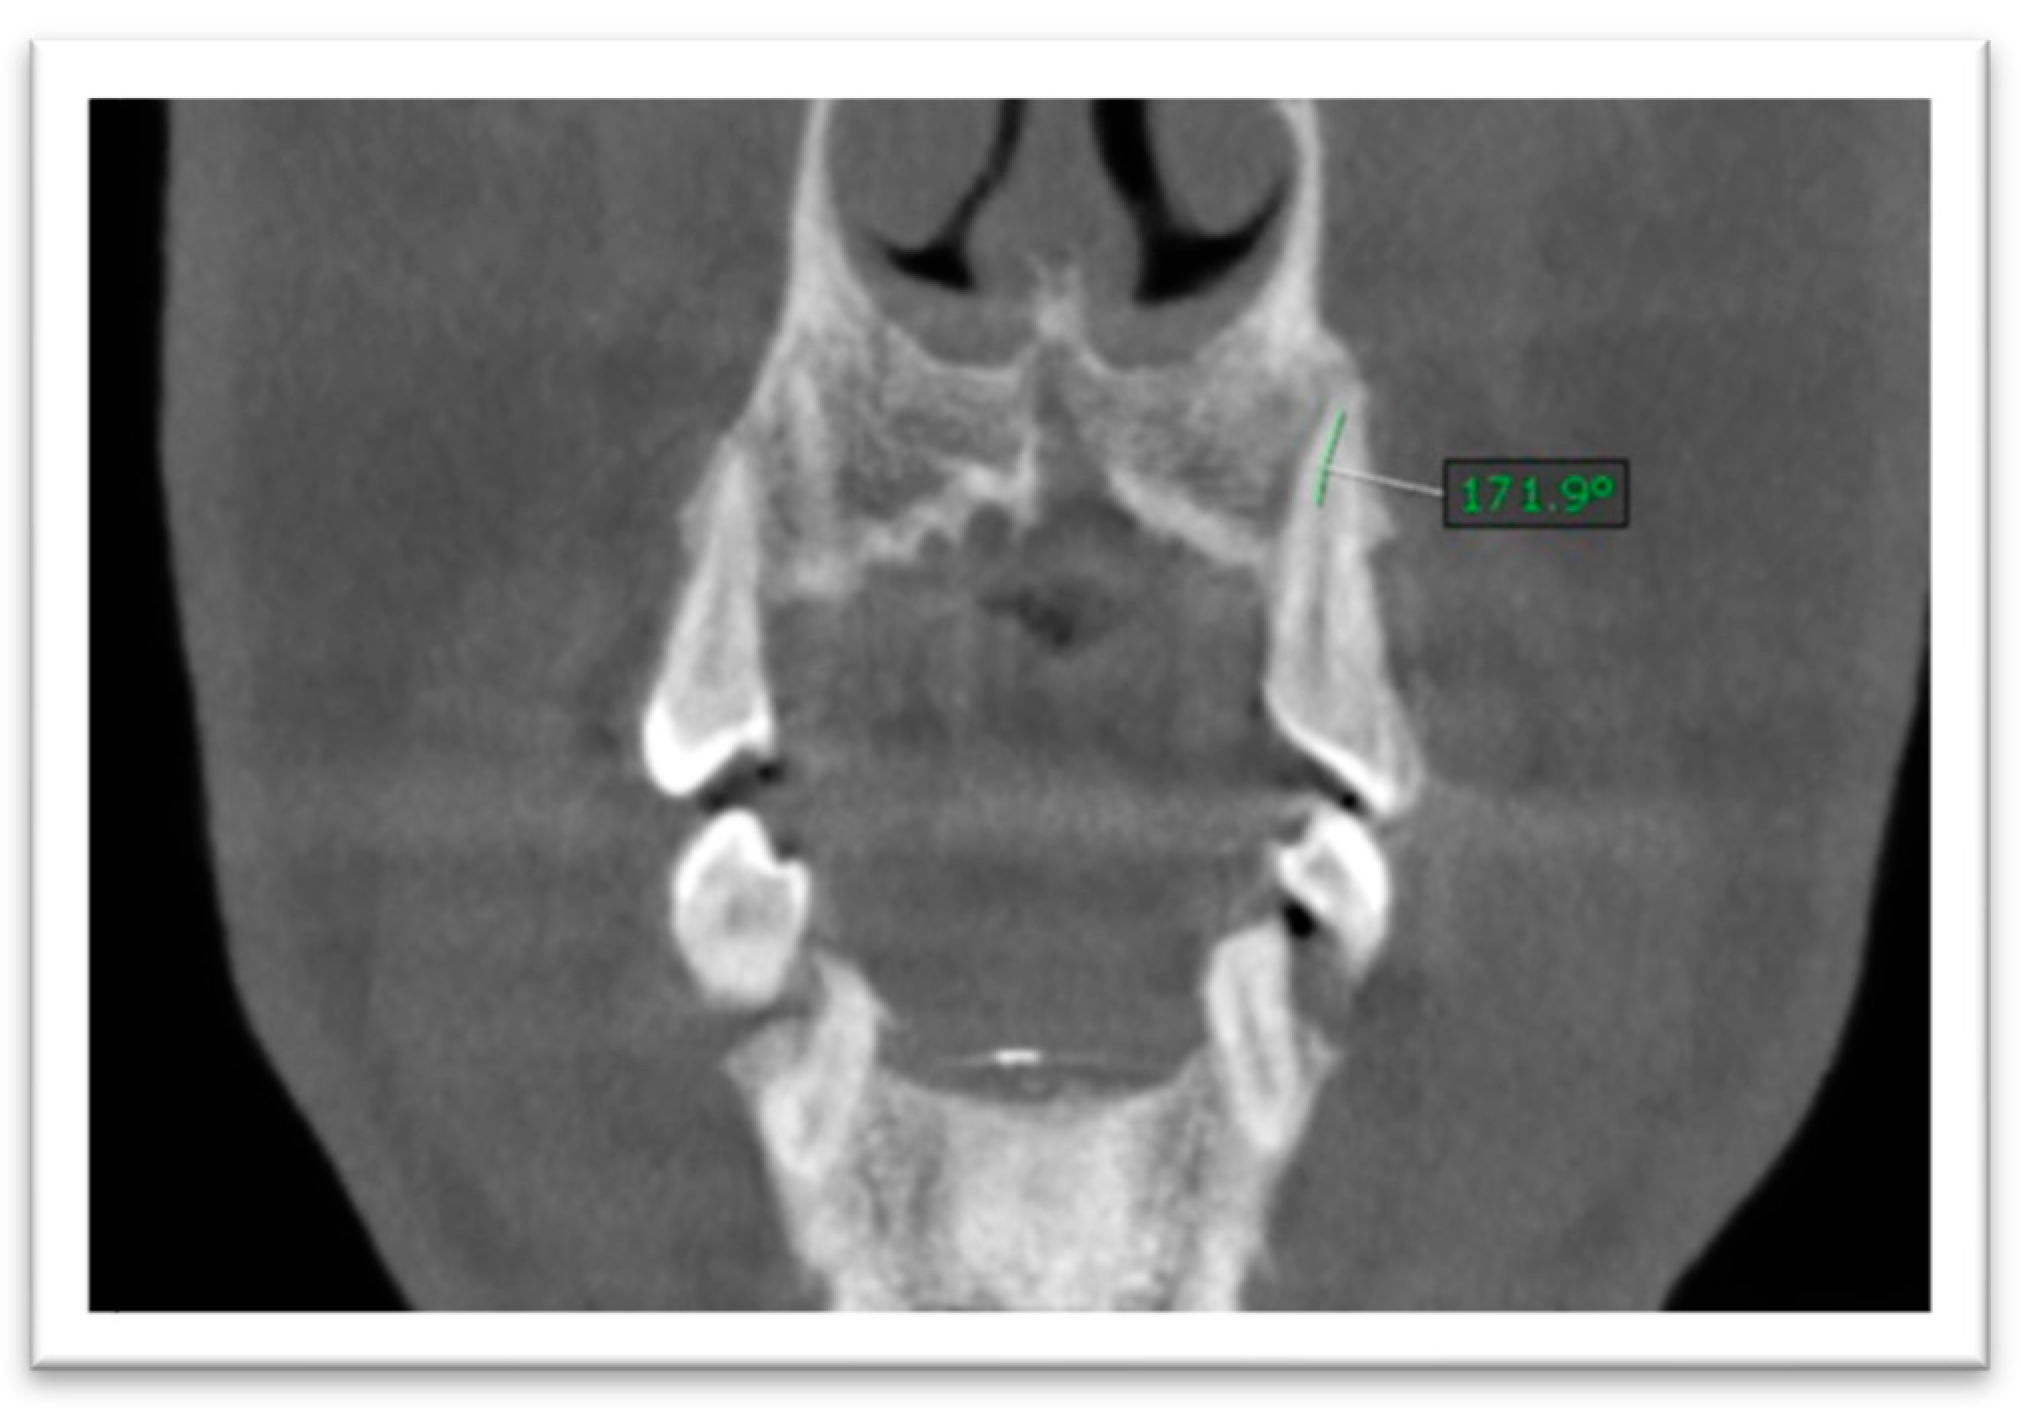

- Since root length was recorded as a straight-line distance, it may slightly underestimate true anatomic length in teeth with pronounced curvature; standardized reorientation was used to capture the maximum tooth length on the plane of measurement. Root canal curvature (angulation) was assessed by scrolling through sagittal and coronal planes. The curvature angle was measured using a Schneider-type approach: a first line was drawn parallel to the canal in the coronal third, and a second line was drawn from the point where the canal began to deviate to the apical foramen; the acute angle between these lines was recorded (Figure 4 and Figure 5). The curvature was categorized as mild (≤5°), moderate (5–20°), or severe (>20°) [22].